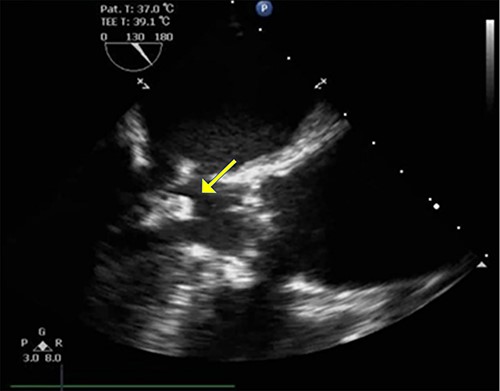

An 86-year-old woman with a history of hypertension and hyperlipidemia presented to our hospital with episodes of syncope lasting several minutes. On admission, her consciousness was clear, and there were no significant neurological findings on physical examination. Electrocardiography showed sinus rhythm at 79 bpm. Laboratory findings showed no abnormalities in electrolytes or anemia that could cause syncope. The coronary angiogram showed 90% stenosis of the right coronary artery (RCA). Transthoracic echocardiography (TTE) and transesophageal echocardiography (TEE) both showed a mobile mass with a maximum diameter of 12 mm on the anterior annulus of the mitral valve (Figs 1 and 2). TTE showed normal left ventricle (LV) function with an ejection fraction of 60%, LV wall motion was within the normal range and no significant valvular disease was detected. Preoperative chest computed tomography showed severe mitral annular calcification (MAC) (Fig. 3).

TEE in the left ventricular outflow tract view shows an echo-dense mass measuring ~12.8 mm × 12.9 mm arising from mitral annular calcification.